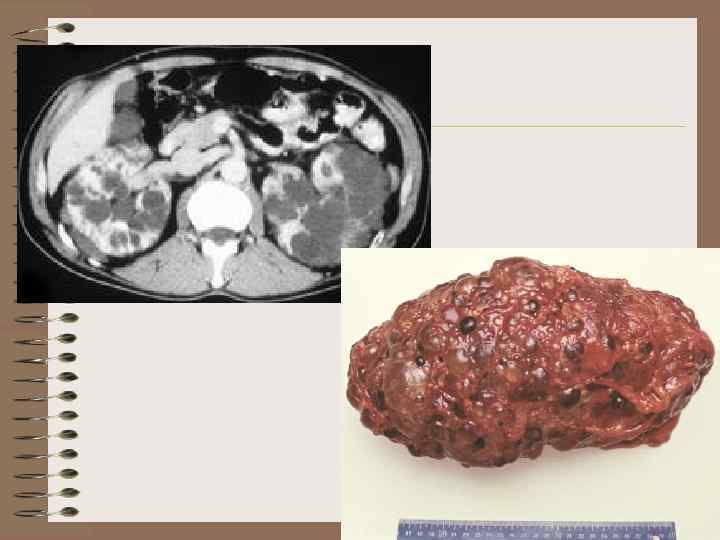

Взрослый тип поликистоза • • крупнокистозный тип передается по аутосомно-доминантному типу, встречается с частотой 1 на 1000 человек, медленно прогрессирует • Клинические проявления появляются после присоединения осложнений, в возрасте 30 лет и старше • Средняя продолжительность жизни после первых клинических проявлений – 14 лет

признаки поликистоза • 2 - сторонность и асимметричность процесса • Увеличение размеров почки • Наружный контур четкий, волнистый, полицикличный • Множественные кисты в паренхиме и почечном синусе • Уменьшение объема паренхимы • Сдавление, уменьшение, деформация срединных структур • 19%-сочетание с кистами печени

Рентгенологические признаки взрослого варианта поликистоза • • • Двустороннее и асимметричное поражение Высокое расположение почек Увеличение всех размеров почки Неровность контуров Увеличение расстояния между верхними и нижними малыми чашами • Смещение лоханки в почечный синус • Изменение оси и деформация больших и малых чаш

Типы деформации чаш при поликистозе взрослых • Сближение, раздвигание, перекрест • Удлинение и сужение, укорочение • Деформация сводов: «клешня рака» , округление, лепесток, серп, конус • Расположение в виде оси колеса •

УЗИ – взрослый вариант поликистоза

Поликистоз, взрослый тип